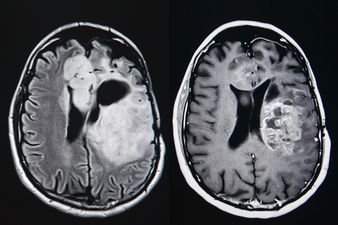

I have a tumour in my brain, and I’m happy about it